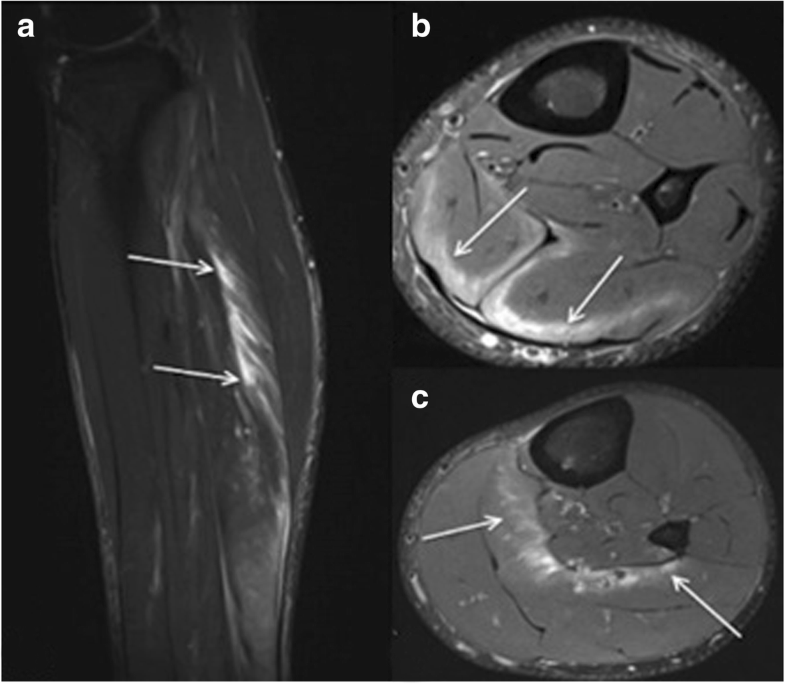

a MRI scan of the left thigh after surgical reconstruction of a skin Thigh Muscle Surgery There are nonsurgical and surgical treatment options available for thigh muscle injures involving a tendon avulsion, or a complete tear. A thigh muscle strain or quadriceps strain is a tear in one of the quadriceps muscles at the front of the thigh. The quadriceps muscle is very powerful, therefore the tendon retracts proximally (up the thigh) and becomes harder to. Thigh Muscle Surgery.